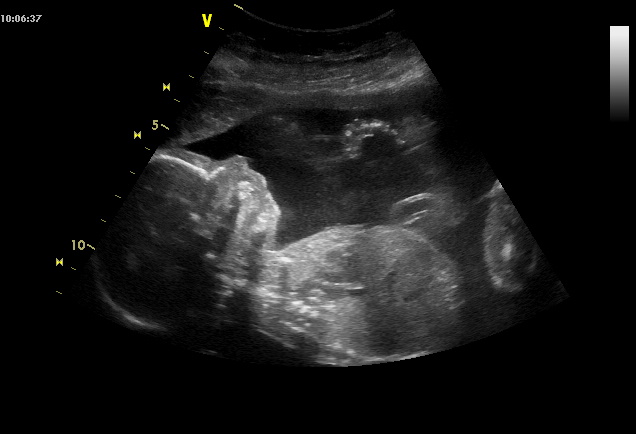

V pondělí jsme byli na speciálním vyšetření u pana doktora. Malý je naprosto v pořádku a viditelně mu náš zájem o něj dělá dobře, protože pěkně ukázal vše, co měl a navíc ještě prstíčky v pusince. 🙂 Musím říci, že to bylo strašně krásné a nečekané, když to udělal 🙂 a nejlepší na tom je, že to máme natočené na video! 😀

Poté nám pan doktor opět potvrdil, že budeme mít chlapečka. 🙂

Lucinka právě prožívá 21. týden těhotenství. Jak roste její miminko v bříšku a co se děje s ní?